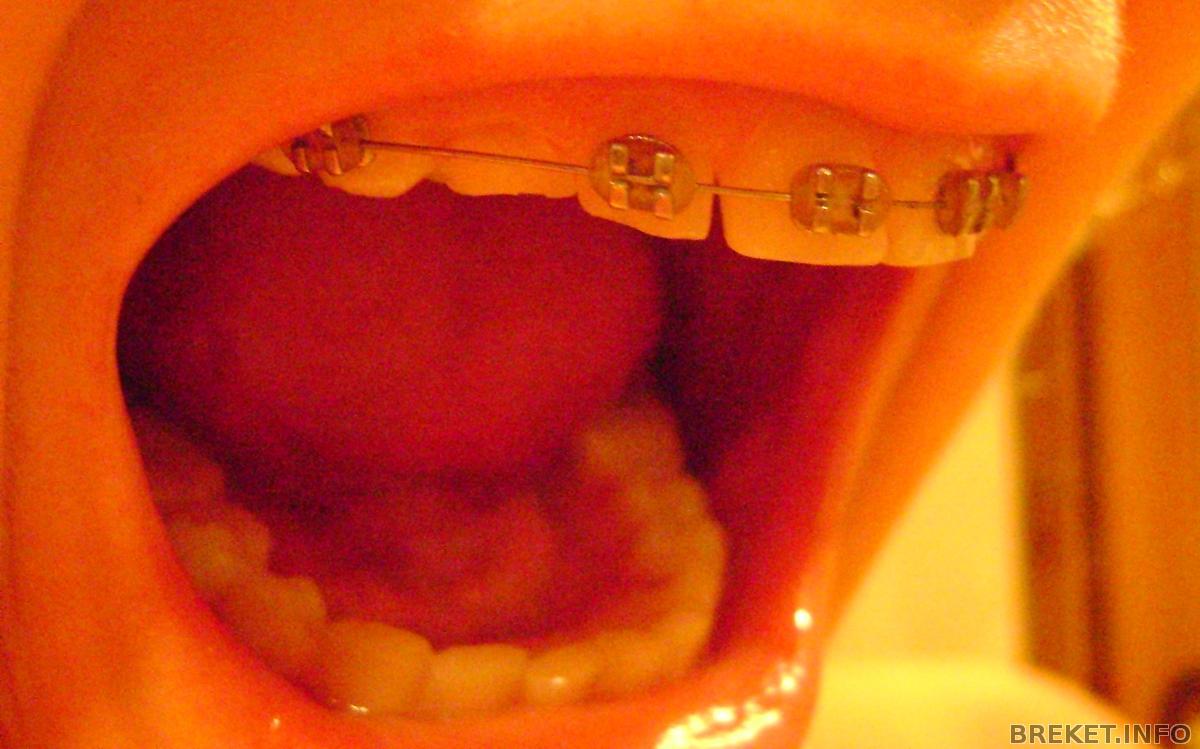

только вышла от врача